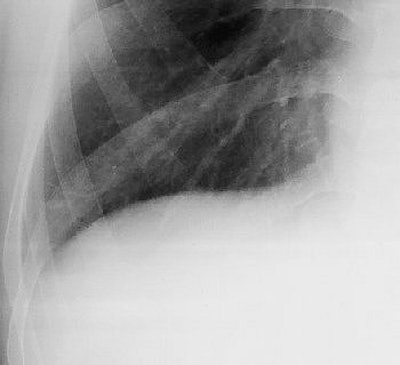

![]() |

| Image A. Paradoxical response to antituberculous medication for tuberculous pleural effusion in a 29-year-old man. Magnified frontal chest radiograph, obtained a month after detection of right pleural effusion, shows that the pleural fluid has disappeared. No lung nodule or mass is evident in the right lower lung. |